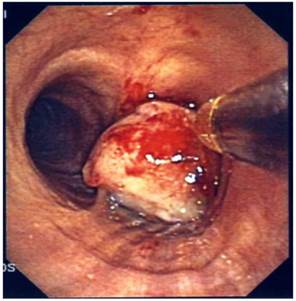

Figure 8

Removal of endobronchial tumor with loop.

J Cancer Image

Recent ACCP Lung Cancer Guidelines mention several interventional bronchoscopic modalities for palliation of dyspnea due to inoperable malignant CAO.[28] The results of the present prospective, controlled study confirm the considerable benefit of interventional bronchoscopic management of such patients and make an argument that patients with malignant CAO treated endoscopically have less dyspnea, better QoL, improved physical function and longer survival than patients with oncologic treatment alone. Combined interventional and oncologic treatment should be considered in any multidisciplinary cancer care program and offered to all patients with lung cancer and inoperable CAO, especially when post-obstructive atelectasis is present. Since such an approach is often limited by the lack of interventional equipment and skills, the urgent need for respiratory physicians' training in therapeutic bronchoscopy and development of interventional units is also highlighted.[29] (Figures 3-8) Additional treatment with radiotherapy could be used based on the patient performance status and local interventional prior or after stent placement-debulking.[30-36] Multimodality treatment is necessary for patients with central tumors local treatment should be accompanied with systematic treatment when possible.